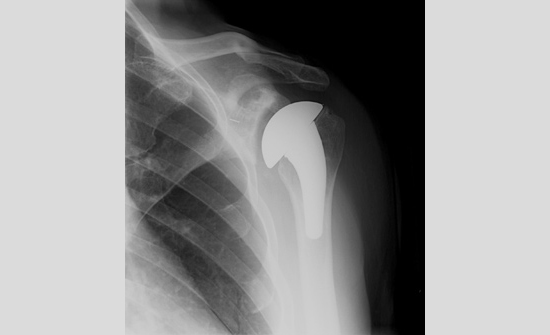

Total shoulder arthoplasty

(Fig. 8) Post-operative x-rays of a 57-year-old male with advanced osteoarthritis.